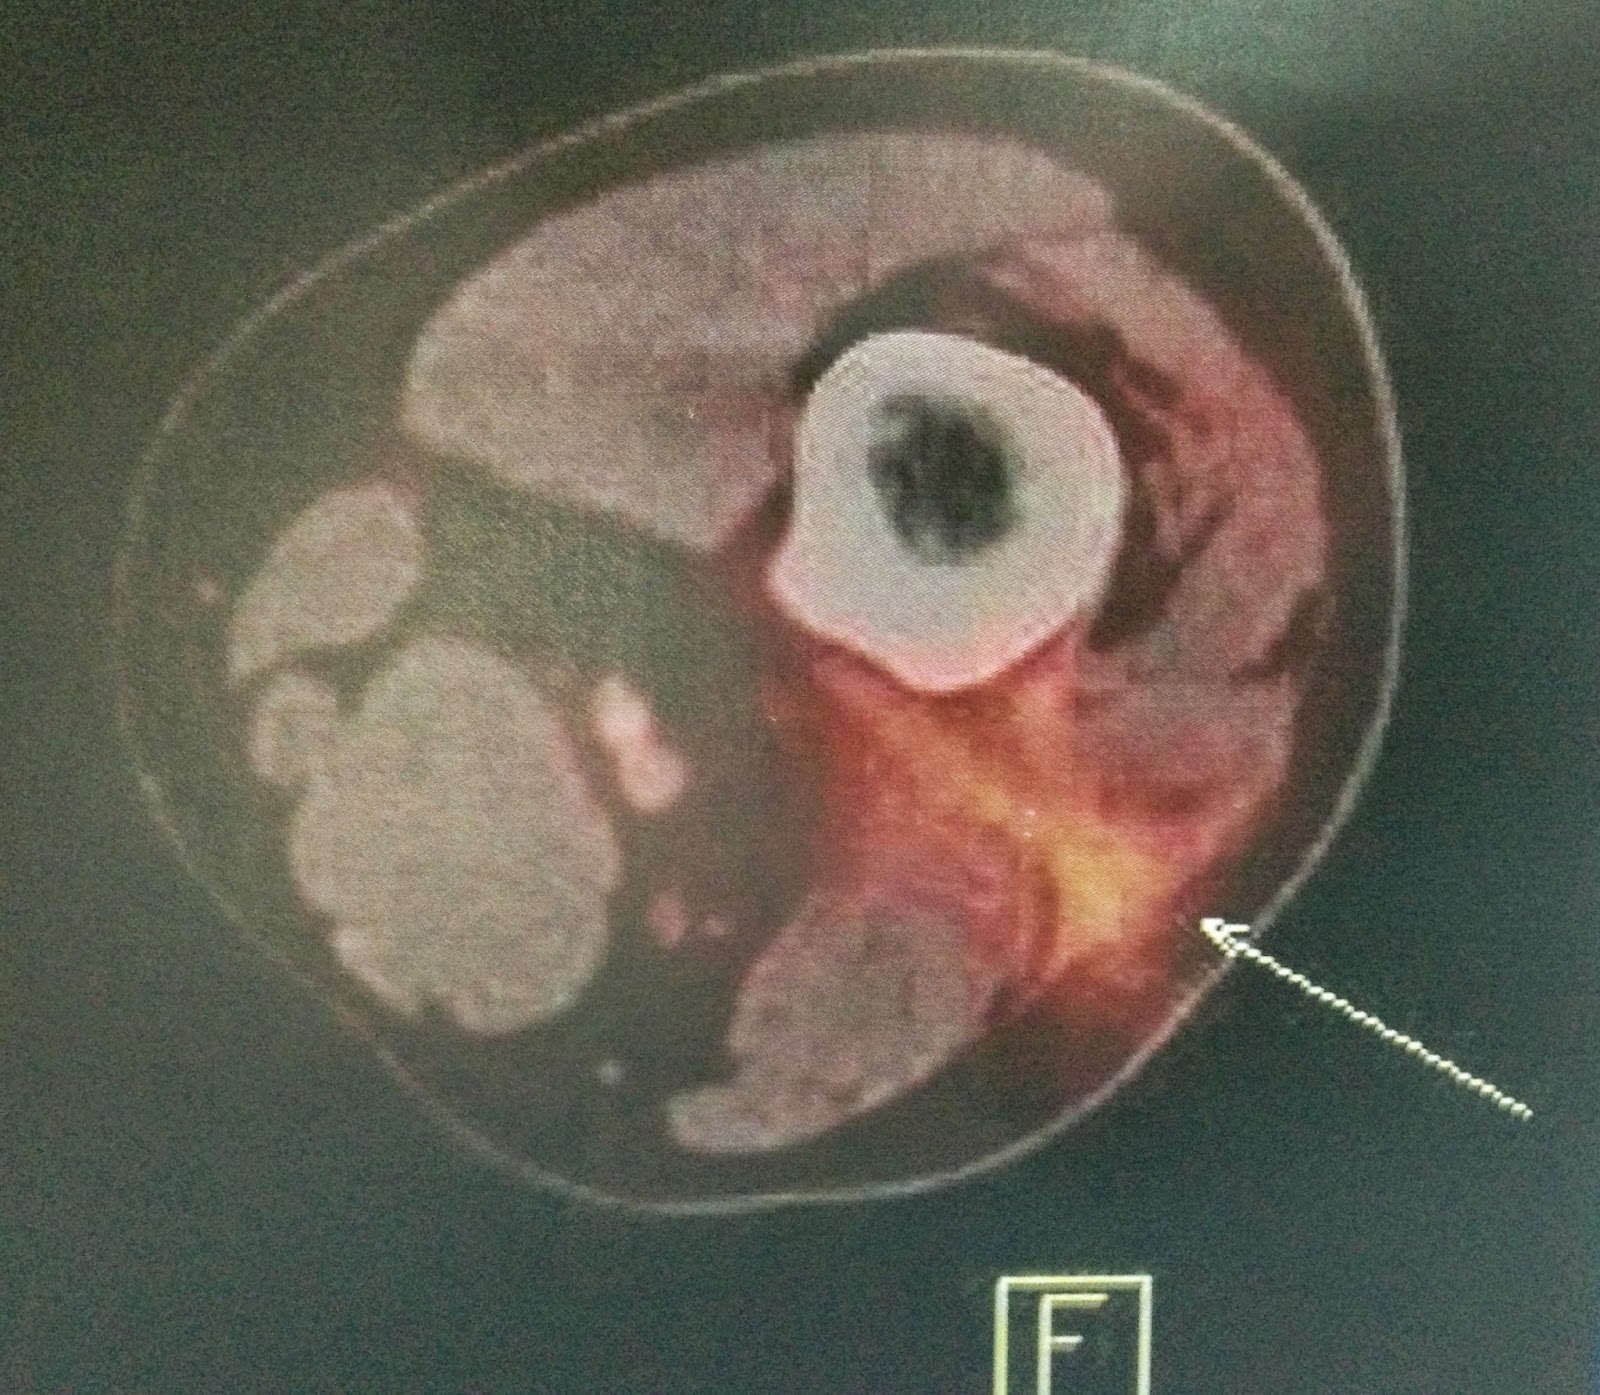

CT Scan of Knee Joint showing Tumor extent. | Open-i

My Image 15